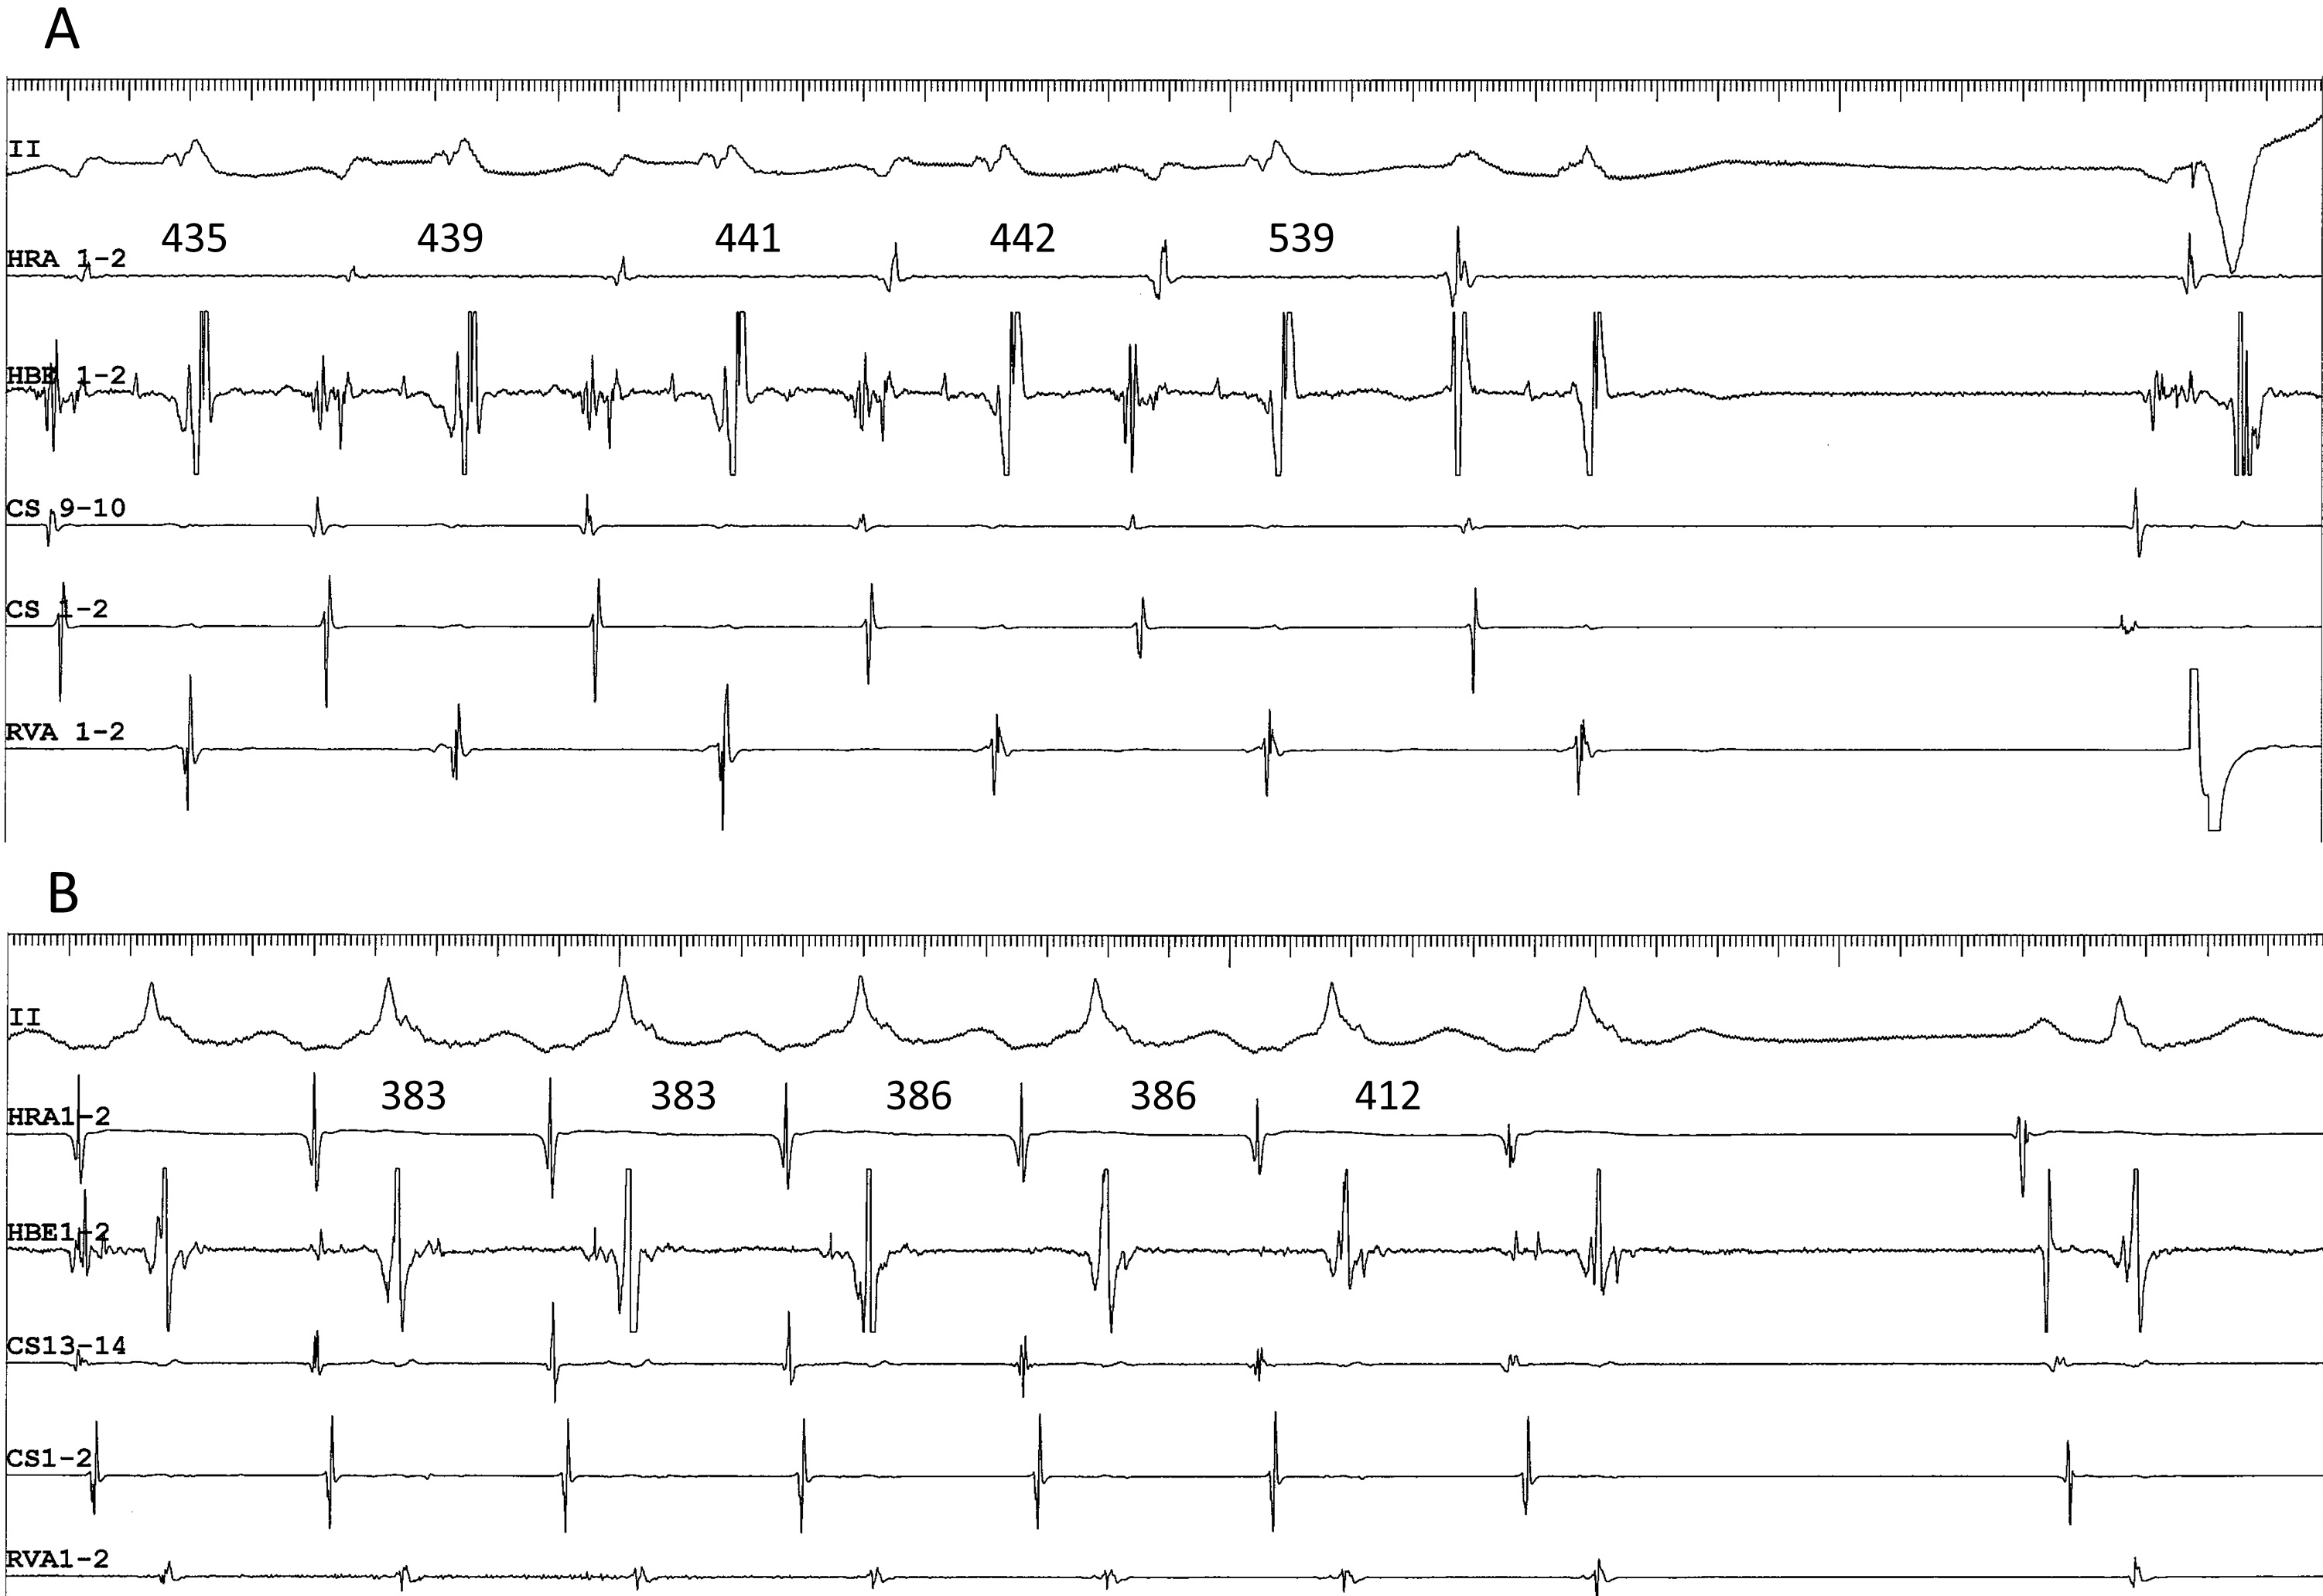

Fig. 6.Termination of superior-type (A) and inferolateral fast-slow (B) AVNRT, following 4- and 10-mg boluses of ATP, respectively. (A) Tachycardia with the earliest site of atrial activation in the His bundle electrogram (HBE1-2), ending with an ectopic atrial event that followed the interatrial interval of 539 ms, longer than the tachycardia cycle length, suggesting that the tachycardia was terminated by retrograde block (or slowed by a retrograde delay) in the superior SP, immediately before the ectopic atrial cycle. (B) Tachycardia with the earliest site of atrial activation in the proximal coronary sinus (CS13-14), slowing in association with a prolongation of the VA interval, and terminated in an “A no V” ending, suggesting that the termination was due to retrograde block in the right atrial, inferolateral SP. Numbers above the high right atrial (HRA1-2) channel indicate the interatrial intervals. II, surface electrocardiogram lead II; CS13-14 to 1-2, proximal to distal coronary sinus; RVA, right ventricular apex.